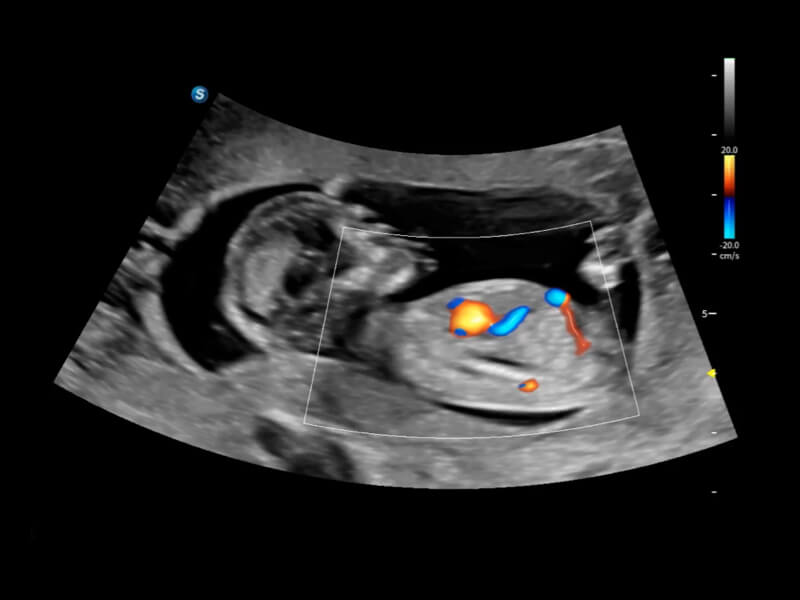

丰富的血流动力学检测技术,可在不同医疗场景中高效捕捉血流信号,助力临床诊疗。

在传统血流的基础上优化扫查和算法策略,能够更好的抑制组织信息,提炼红细胞运动信息,得到更高帧频,高灵敏度和分辨率的血流信号,还原更真实的血流动力学。

通过光照模型,使二维血流显示出立体的效果,增加血流的敏感性、成束性,减少外溢。可以和其他不同的血流技术联合使用,融合不同技术的优势。轻松应对微小血管,增强血流的立体效果,提升视觉敏感性。